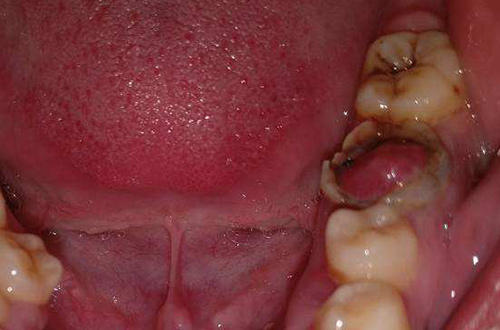

之前去咸阳海涛口腔医院洗牙的时候,洗牙的医生给我说我后面的牙齿坏了,可能需要进行简单的治疗一下。当时我没觉得有什么,没在意,后来海涛口腔电话回访的时候还问过我,都被我敷衍过去了。一直到前些天我觉得牙齿越来越敏感,越来越痛了,我就又去了海涛口腔,这个时候已经过去了有一年多了。这个时候我的那个坏了的牙已经没得救了,医生说需要拔出,在做种植牙。

这个方案其实我来之前就想到了,还是怪自己对自己的牙齿不上心导致的,如果我可以早早的听医生的话进行治疗,可能就不需要拔牙种牙了。但是后悔也没用了,现在只能做种植牙了。